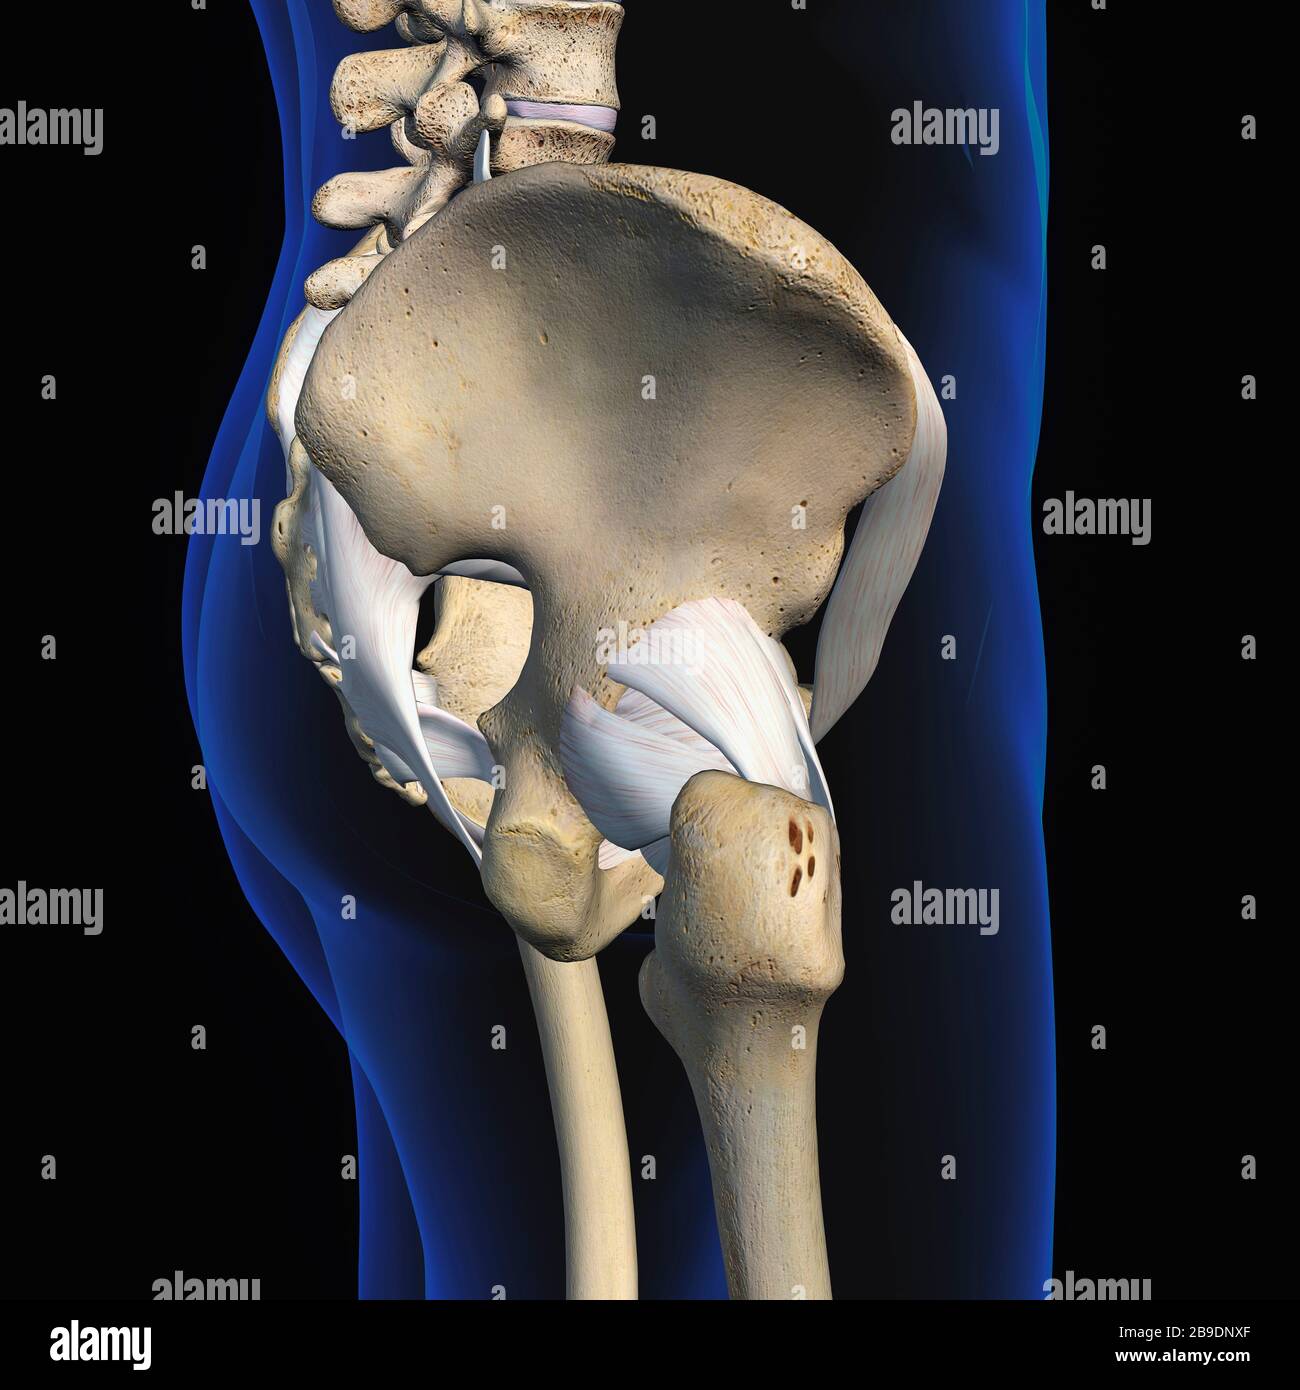

RFWW2CNW–Die männliche Anatomie, Gliedmaßen und hip Muskel- und Skeletterkrankungen Systeme, mit interner Muskelschichten. Vorder- und Rückansicht. schwarzen Hintergrund. 3d-Abbildung.